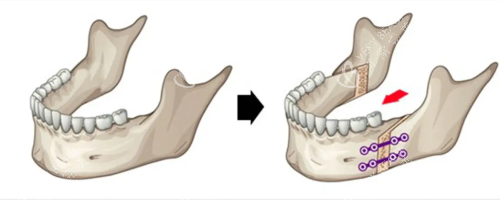

面诊那天,医生拿着我的CT片,指着骨头说:“你这是上颌前突+下颌后缩,得做双颌手术——上颌截骨后移,下颌截骨前移。”我听得云里雾里,只问了一句:“能让我侧脸不凸吗?”医生笑:“术后你的侧脸会立体很多,但得做好心理准备:前三个月肿得像猪头,半年才能正常吃饭。”我咬咬牙:“做!”

术后前三个月,我像“养伤正规户”——每天喝粥、吃蒸蛋,连苹果都得打成泥。第四个月开始,能嚼软饭了,但硬的东西还是不敢碰。第六个月复查时,医生拿着我的对比照说:“侧脸变化非常大,上颌收了5毫米,下颌前移了3毫米,现在比例很协调。”